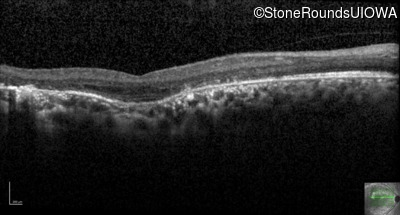

Optical Coherence Tomography - Right - 5/200

Exemplar / OCT Stack

OCT Stack